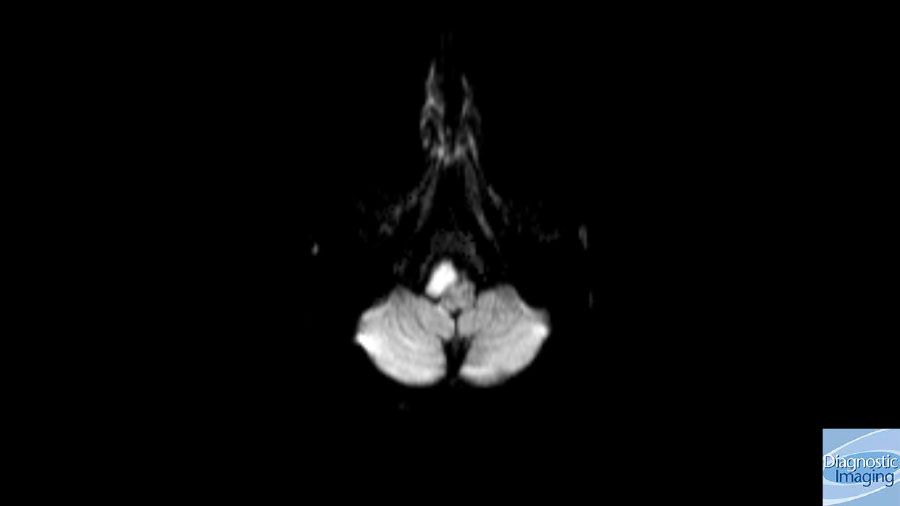

Case History: 13-year-old male with complaint of headache and hearing loss.